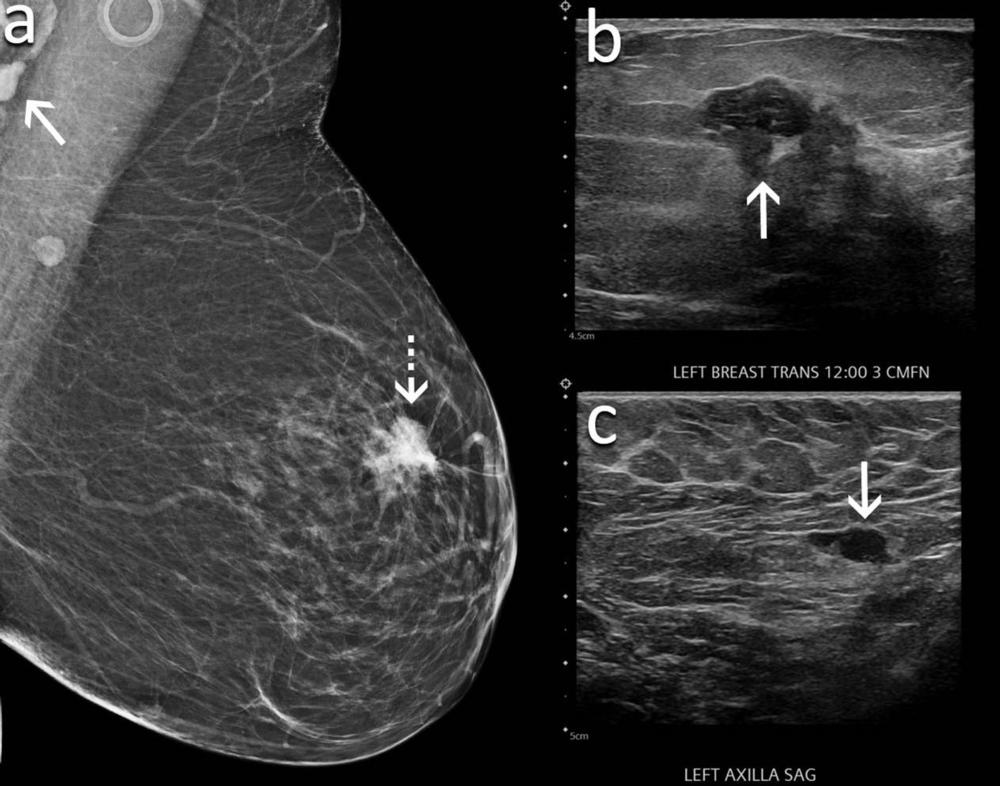

Figure 3. A 60-year-old woman presents for screening mammography nine weeks after receiving her second dose of the Moderna COVID-19 vaccine. (A) Mediolateral oblique view of the left breast demonstrates an irregular mass in the superior left breast (dash arrow) and a dense lymph node in the left axilla that is incompletely visualized (arrow). Sonography demonstrates (B) an irregular hypoechoic mass in the breast (arrow) that corresponded to the mammographic finding and (C) a lymph node with eccentric cortical thickening measuring 6 mm (arrow) in the axilla. Biopsy of the mass yielded invasive ductal carcinoma and biopsy of the lymph node yielded metastatic carcinoma.

High-res (TIF) version